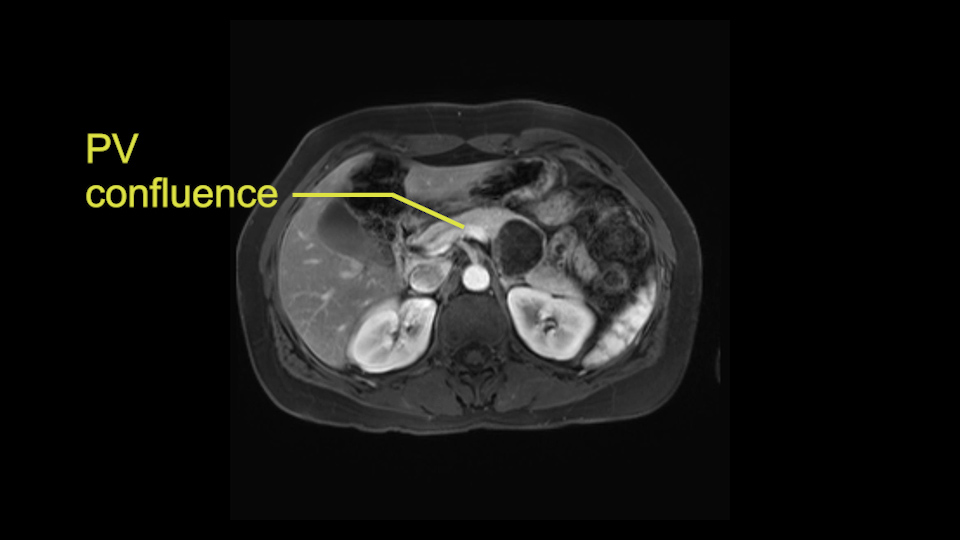

The slowing down moments or considerations that I give when I look at the scan and plan my distal pancreatectomy is how far away the tumor is to the portal vein and do I have to formally create a tunnel behind the pancreas on top of the portal vein or do I have to take the pancreas further to the left of the portal vein or the patient’s left of the portal vein. So here I can see that here is the tumor here. I can see that the tumor is a fair way away to the patient’s right and so I will likely not have to take or create the tunnel formally in this procedure. And that speaks a lot to the resection margins. So its important when you’re doing a distal pancreatectomy or any procedure potentially for oncologic reasons to get clearance of the tumor and to take the tumor kind of intact.

The second slowing down moment or consideration I give to a distal pancreatectomy is the anatomy of the portal vein and the splenic artery. And so I look here and the anatomy is pretty straightforward. The splenic vein comes off normally and runs behind the pancreas and I can see the artery superior to that, again coming off in a normal manner from the celiac axis. So those two things, the portal vein and the splenic artery will be taken normally in this procedure.

Key features that I look at the imaging are: first I look at the distance between the cyst and the portal vein SMV confluence. So there are guidelines for this, they call the Yonsei guidelines, to decide to do it laparoscopically or open and basically it says that if it’s a cancer, at least a centimeter away from the celiac trunk or the venous confluence. This is a cyst. So maybe you could stretch that a bit, but you don't want to get into trouble there. So for this cyst if you look at it, it's nicely away from the confluence.

So unfortunately I cannot show you a coronal view but you can see it easily on this scan, going down first you see the celiac trunk and you see here, quite a nice distance between the celiac trunk and the beginning of the mucinous cyst. And if you go up here and follow down the portal vein confluence you also see a nice distance there.

So what I would normally do in these patients, I would look at the abutment of any other organs, one, which is here, potentially the adrenal gland and two the small bowel. And two, look at the distance from the vessels which I would normally do in a coronal view. So you can easily measure the distance and third I look at the insertion of the inferior mesenteric vein. Now we can probably also see that on here. Although it's better on a CT scan and it's better on a coronal view, you want to know where the inferior mesenteric vein comes into either the splenic or the SMV, because that is typically a very important slow down moment when you mobilize the lower portion of the pancreas knowing where the inferior mesenteric vein comes in either the splenic vein or the SMV. So those are I think the three most important points for the CT scan.

If you hang the pancreas then you move down towards the right side of the patient. You know your first slowing down moment is where the inferior mesenteric vein comes in the splenic vein or into the superior mesenteric vein, you have looked at that at the scan, so you know where to expect it. You can do two things in a procedure where you can preserve the splenic vein, you can preserve the IMV as well. But in this case where you want to do an oncologic resection with splenectomy, you will transect the inferior mesenteric vein.

Moving down to the right, you will encounter the superior mesenteric vein. Definitely a slowing down moment. And that's when you can start to make the beginning of a tunnel. You don't make the entire tunnel. Then you go to the cranial side of the pancreas. Also there you mobilize it fully. The slowing down moment is freeing the hepatic artery and the station 8 lymph node which is there which comes with a routine oncologic resection so you mobilize that off the hepatic artery and then you continue at the superior side of the pancreas, going up to the celiac trunk, taking also the lymph nodes on the left gastric artery and below the celiac trunk. After you've done that, you can complete the tunnel and also hang the pancreas there with a bit of vessel loop. So basically now you’ve got two vessel loops around the pancreas, you can hang the entire pancreas. From that comes, stapling of the pancreas. I typically do that first before transecting any vessels. You can staple the pancreas with various staplers. Depending on the size, if you cut it at the neck, which you should do for oncologic resection. You could probably take a thinner stapler than if you would go more to the left side of the pancreas. There's no conclusive evidence on which stapler to use.